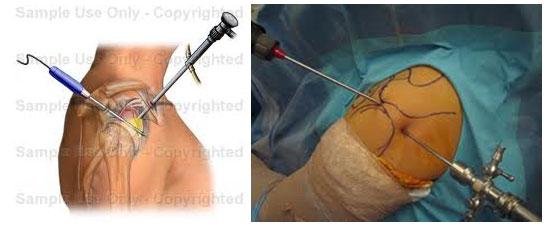

Αρθροσκόπηση γόνατος Παγκράτι, Ορθοπαιδικός Παγκράτι, χειρουργός ορθοπαιδικός Παγκράτι, ορθοπαιδικοί ιατροί Παγκράτι, ορθοπαιδικό ιατρείο Παγκράτι

Ρήξη μηνίσκου Παγκράτι, ρήξη χιαστού Παγκράτι, ορθοπαιδικό ιατρείο Παγκράτι